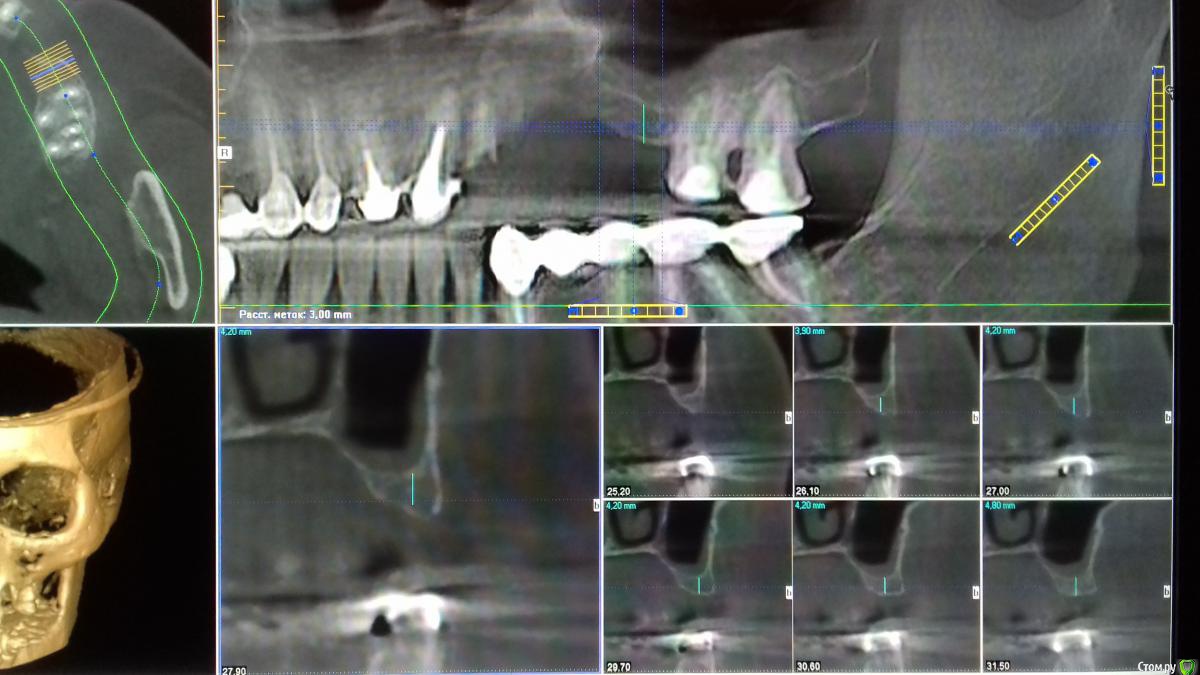

Хью Крейн Опубликовано 4 июня, 2018 Поделиться Опубликовано 4 июня, 2018 Уважаемые коллеги,нужен совет. Изначально план операции был таков:удаление корня 2.2,резекция верхушки корня 2.1, открытый синуслифтинг в области отсутствующего 2.5,вертикальная аугментация в области 2.3,2.4,2.5,консервация лунки 2.2. Закрытый остиум ставит в тупик. Пациент-курильщик. Недавно перенесено респираторное заболевание. 3.3 удален около 3 мес. назад по поводу локального парадонтального очага. Симптомов синусита не наблюдалось. К ЛОРу бы направить,но грамотного нет на примете. Ссылка на комментарий

Хью Крейн Опубликовано 4 июня, 2018 Автор Поделиться Опубликовано 4 июня, 2018 Как вариант:вторым этапом сделать закрытый без графта,подняв на пару мм и имплант короткий зашинировать в общую конструкцию. Возможно,на момент созревания аугментата Кт перед имплантацией покажет остиум в норме. Мск Ссылка на комментарий